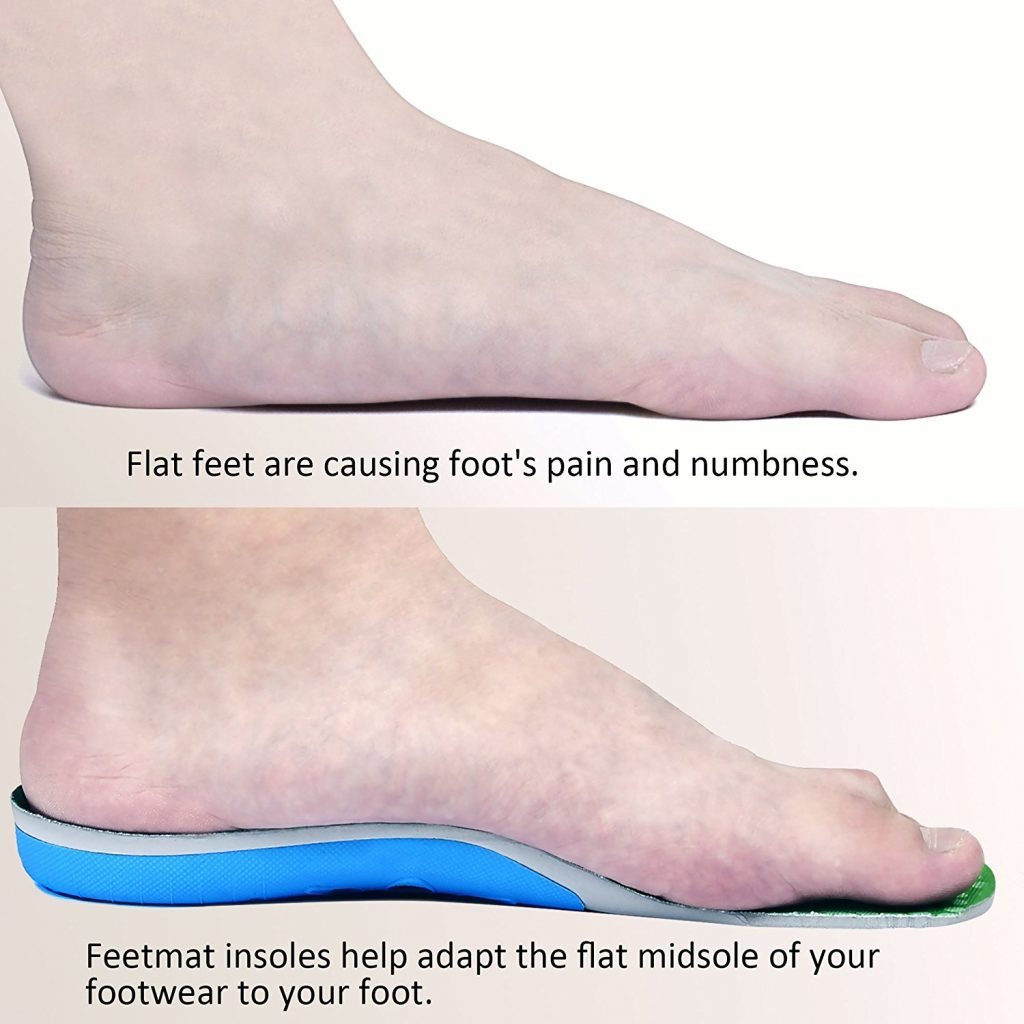

Electo Mania Flat foot orthopedic insole: Buy Electo Mania Flat foot …